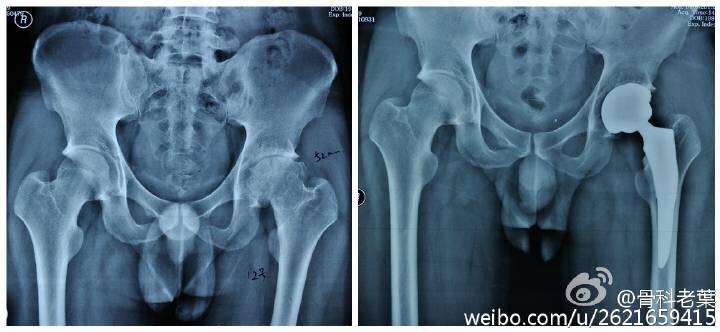

另附典型病例若干: